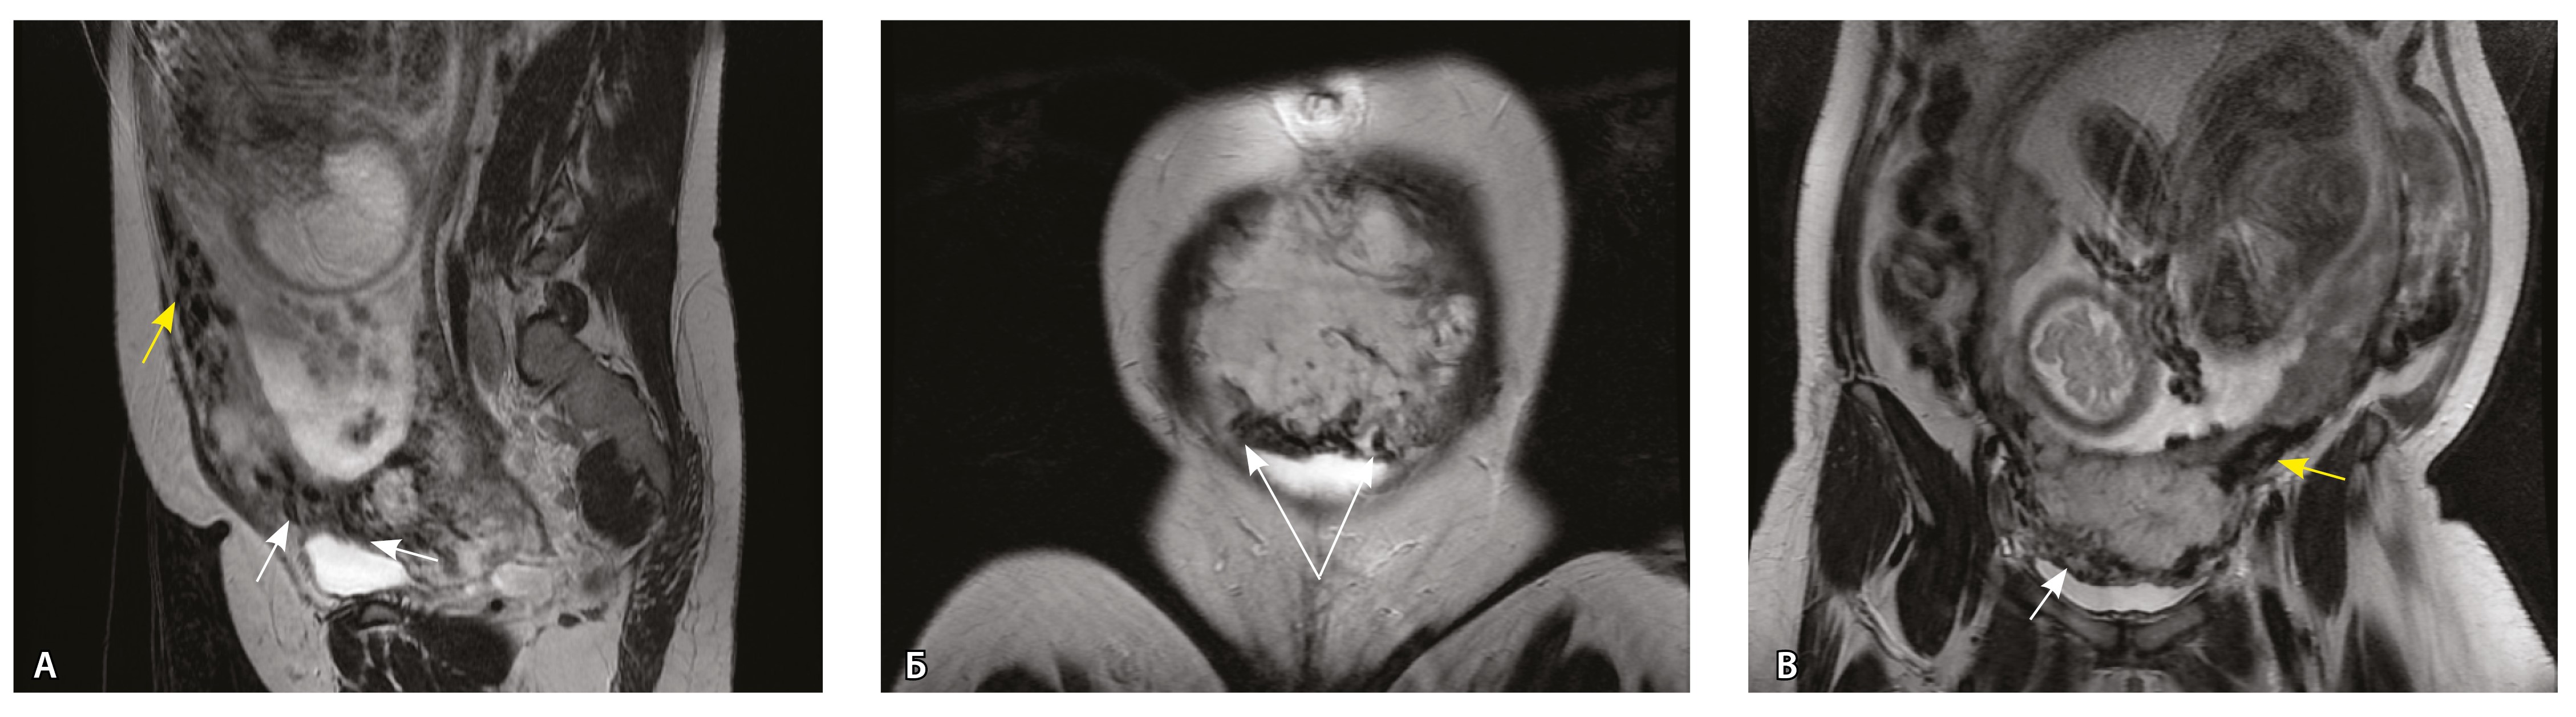

Рис. 4. Беременность 32 недели, pl. accreta, PAS 1 по FIGO. На магнитно-резонансных томограммах в режиме Т2-взвешенного изображения в сагиттальной (А) и аксиальной (Б) плоскостях видны сосуды на границе маточно-плацентарной области, сливающиеся между собой (белые стрелки), без выраженного дефицита толщины миометрия и рубца от кесарева сечения, без признаков выбухания стенки матки. На Т1-взвешенном изображении в режиме подавления сигнала от жировой ткани в аксиальной плоскости (В) выявляется наличие участков повышенного сигнала (желтые стрелки) на границе маточно-плацентарной области, что соответствует геморрагическому компоненту в подострой/хронической стадии (ретроплацентарные гематомы) либо белковому содержимому (фибриноид)

Непосредственное сравнение МР-картины с операционным материалом подтвердило, что полости с геморрагическим компонентом соответствовали ретрохориальным гематомам различной давности, чаще подострой и хронической стадий, которые состояли из гемолизированных эритроцитов, нитей фибрина сетчатого строения, а также замурованных атрофичных ворсин (рис. 5). Следовательно, констатация на МРТ фиксированных геморрагических полостей в маточно-плацентарной области отражает не гиперваскуляризацию стенки матки, а наличие ретрохориальных гематом в подострой/хронической стадии, что следует учитывать в клинической практике.